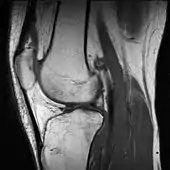

A grayscale MRI of a knee – different gray levels indicate different tissue types, requiring a trained eye.